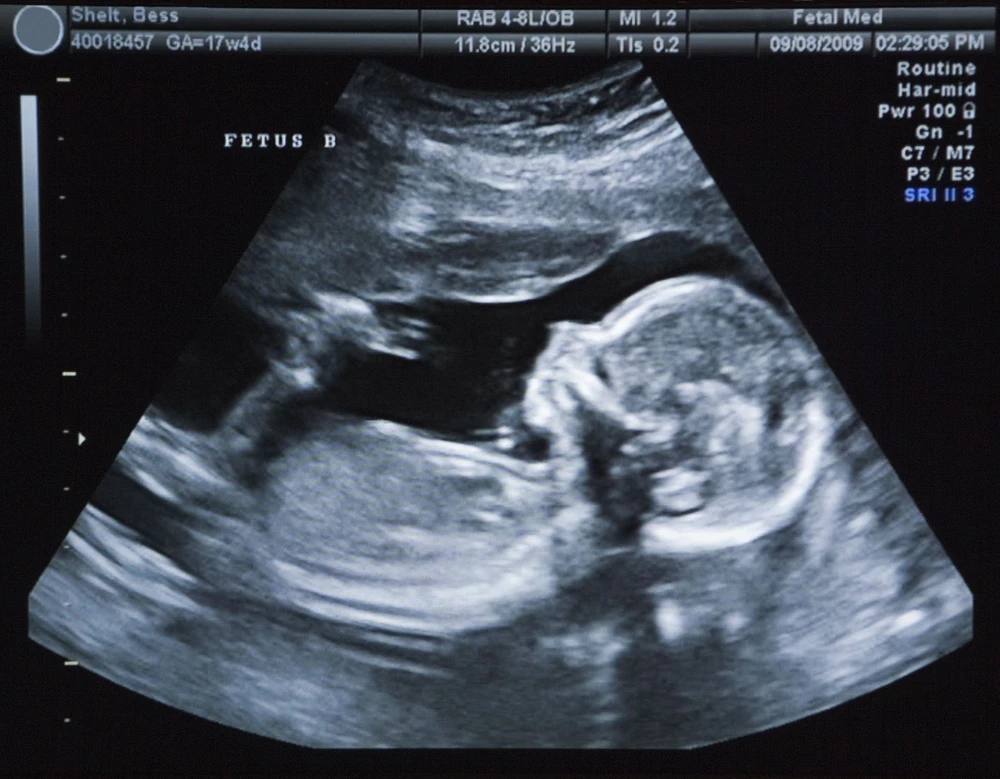

Siêu âm có thể giúp chẩn đoán sớm tình trạng khối u từ trong bụng mẹ. Ảnh minh họa.